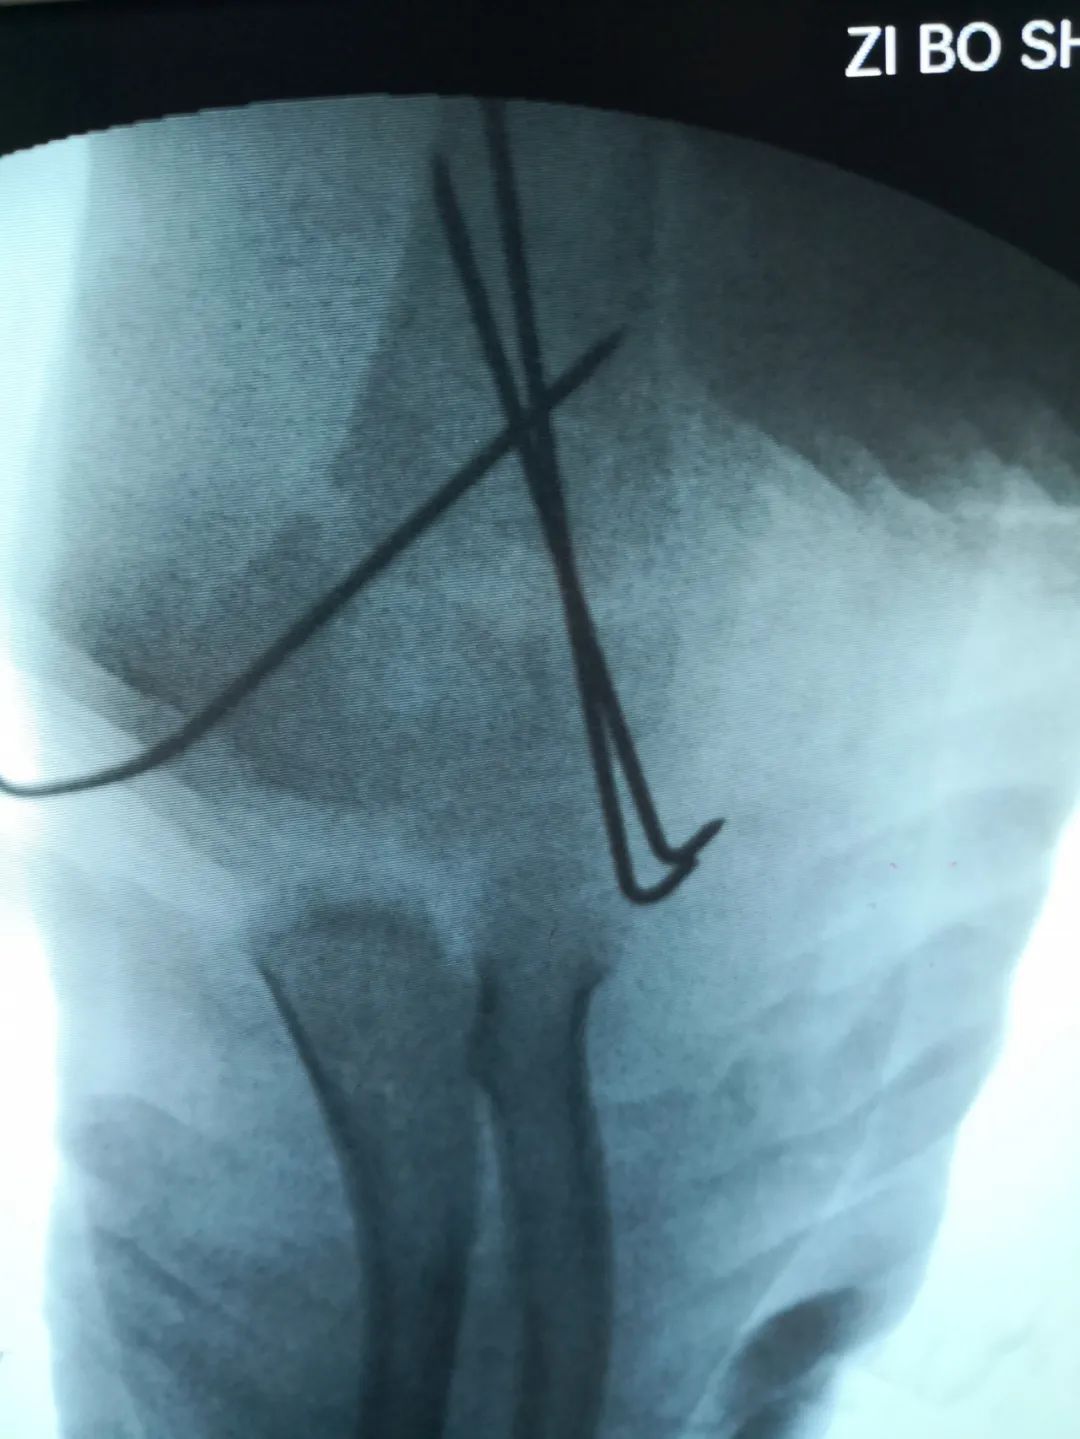

刘法银医生介绍称,经检查,童童诊断为右侧肱骨髁上骨折,软组织挫伤重,伴桡神经损伤,给予‘桡神经探查术+切开复位内固定术’。

“对于另外2例骨折患儿,因未造成神经损伤,给予C臂透视下手法复位闭合穿针内固定手术,不用切口,创伤小,恢复快,术后四周门诊拔出钢钉,免除二次手术取内固定。”刘医生说道。